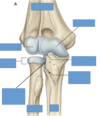

Label this diagram

Label this diagram of clavicle